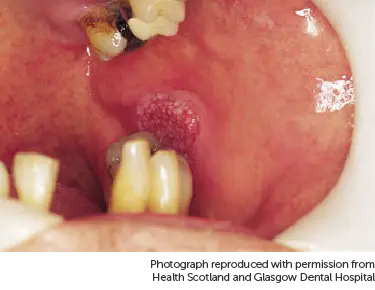

Below is a picture of a red patch underneath the tongue.